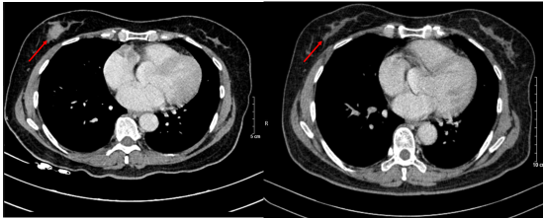

Hình 5.

Hình ảnh MRI u vú trước (bên trái) và sau điều trị (bên phải): Khối ngấm thuốc ¼ dưới ngoài vú phải trên phim MRI trước điều trị hiện không thấy trên phim MRI sau điều trị.

Chụp cắt lớp vi tính lồng ngực: Không phát hiện hình ảnh bất thường ở nhu mô vú phải.

Hình 6.

Hình ảnh CT u vú trước điều trị (bên trái) và sau điều trị (bên phải): Trước điều trị: 1/4 dưới ngoài vú phải có nốt đường kính 20mm, bờ ranh giới không rõ, ngấm thuốc sau tiêm. Sau điều trị: Không phát hiện hình ảnh bất thường ở nhu mô vú phải.